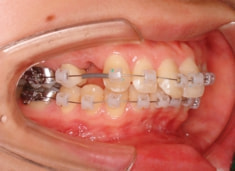

治療開始時

治療開始から1年7ヶ月後